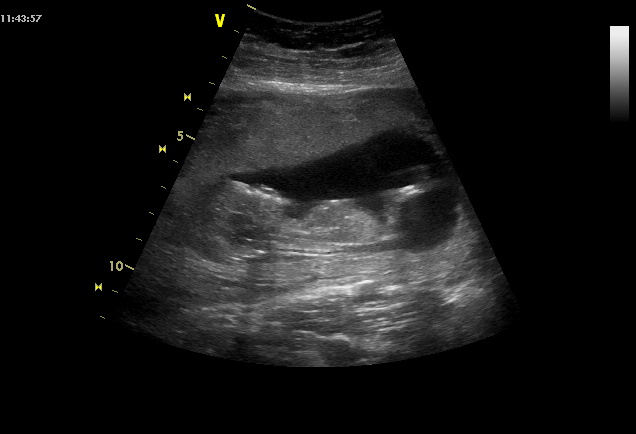

Ahoj holčiny, tak jsem zpět v práci, screening dopadl dobře, riziko prý minimální, srdíčko a hlavička pěkný, přikládám fotku. Je to bomba! Byl i manžel, líbilo se nám to, vrtěl tam sebou, kopal nožičkama, ručičkama, nádhera!!! Jo a je o týden starší, takže jsem dnes 13+0, máme 6,5 cm :D